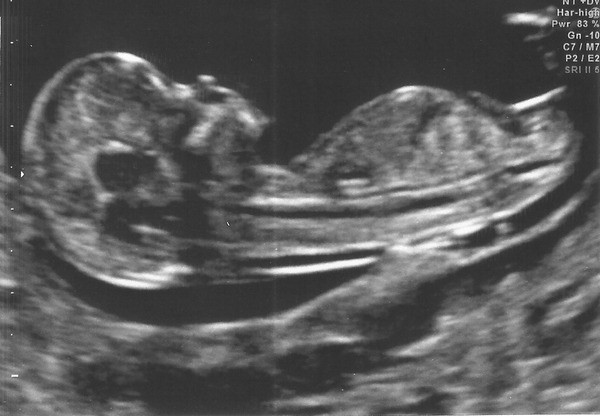

And here's the scan pic from friday.

Paranoid What a fantastically clear scan pic! Glad all is well and your brother took the news well. It can't of been easy for you.